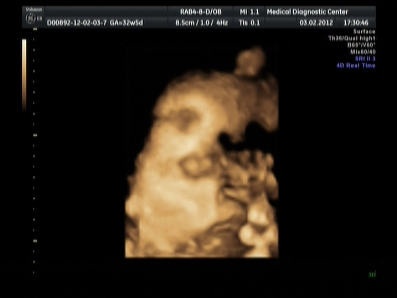

Еще малышка не захотела показывать в этот раз личико,закрылась и все.

Здесь видно немножно сбоку личико,но все равно не то что я ожидала...